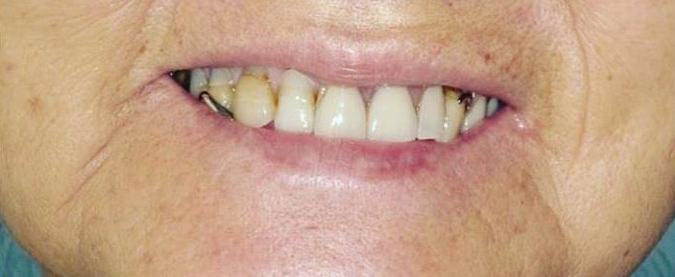

Can just four implants replace all of the teeth on the top or the bottom of your mouth? Thanks to advances in dental implant technology, that answer is a resounding yes.

Believe it or not, tooth loss is extremely common among adults, especially as we age. In fact, more than 35 million people in America are missing all of their upper and/or lower teeth. Rather than living with the discomfort and hassles of dentures, many people are opting for what is called “all-onfour” dental implant restoration.

Here’s where it gets really interesting: You do not need a dental implant for each and every one of your missing teeth. All you need is four precisely placed implants on the top of your mouth, and four on the bottom, to restore your full smile. That’s the beauty of the all-on-four. And because the implant is made of titanium, it has the unique ability to fuse to living bone and function as part of it. So eventually, the dental implant becomes part of the jawbone and serves as a strong, long-lasting foundation for your new teeth.

Thanks to advances in dental implant technology, just four implants can replace all of the teeth on the top or the bottom of your mouth.

this bone fusion has another important benefit: it prevents future bone loss in the jaw. This helps to maintain a more youthful facial structure – and better oral health. But perhaps the biggest surprise about the all-on-four is how quickly it can transform your life.